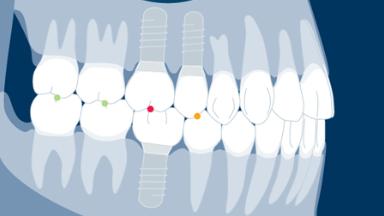

It is also important to be able to provide base line information about the prosthesis against which you can compare the condition of prosthesis over time.

- list the step by step protocol for delivering an implant-supported restoration

- describe how to evaluate a restoration and rehearse its assembly

- describe the steps of trying-in and verifying that a restoration is clinically acceptable

- describe the clinical techniques for fitting both screw- and cement-retained restorations

- indicate appropriate oral hygiene advice and techniques for implant restorations as well as list the baseline documentation that needs to be recorded for continuing care